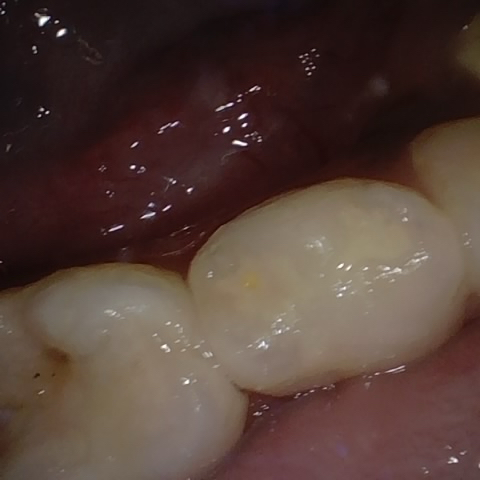

Annotated as "Good"